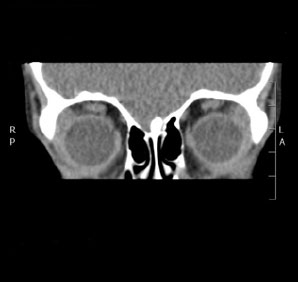

Tomografía computarizada Órbitas

< Volver a "Tomografía Computarizada (TC) con Inteligencia artificial"Está indicado para el estudio de los globos oculares o de los huesos de las órbitas (traumatismos).

Cuando queremos estudiar los globos oculares, en algunas ocasiones necesitamos la inyección de contraste endovenoso, por lo que se debe venir con 6 horas de ayunas (3 horas en pacientes diabéticos), pudiendo beber agua y sin que sea necesario suspender ningún tratamiento que pueda estar tomando.